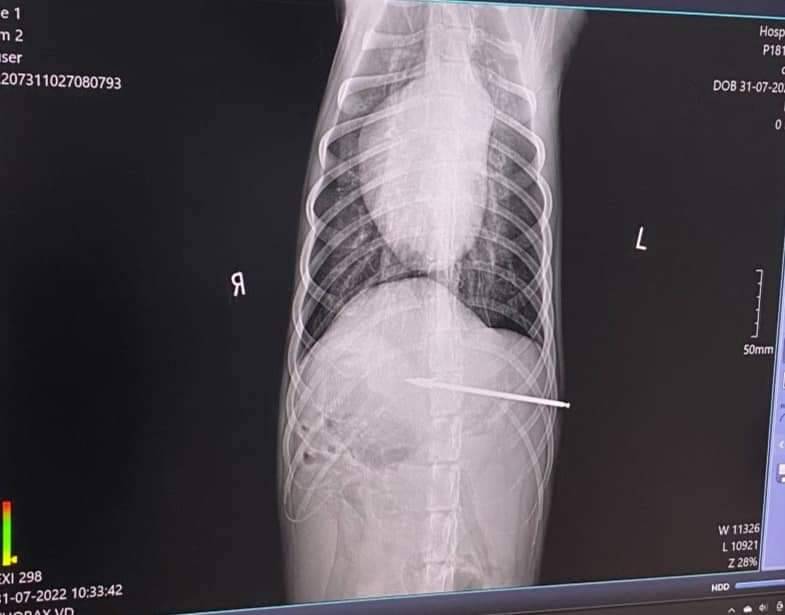

หลังจากนั้นนายไพศาลกับน้องสาว ได้ช่วยกันอุ้มเจ้าดีน ที่ลำตัวยังมีลูกดอกฝังในและอยู่ในอาการสลบ ขึ้นรถกระบะไปรักษาที่โรงพยาบาลสัตว์ เอกชนแห่งหนึ่งในตัวเมืองเชียงใหม่ ก่อนจะให้สัตวแพทย์ ผ่าตัดเอาลูกดอกออกสำเร็จ ใช้เวลานานกว่าครึ่งวัน จึงสามารถนำลูกดอกออกจากตัวเจ้าดีน พบว่าเป็นลูกดอกเหล็กดัดแปลง จากซี่ลวดล้อรถมอเตอร์ไซค์ฝังในลำตัวลึกกว่า 10 ซม. ซึ่งหมอบอกว่าโชคดีที่ไม่โดนอวัยวะสำคัญ หลังจากนั้นทั้งสองจะพาเจ้าดีน กลับมาที่บ้าน และนำลูกดอกที่หมอผ่าตัดออกมาเป็นหลักฐาน ไปแจ้งความกับพนักงานสอบสวน สภ.สารภี เพื่อติดตามตัวหาคนที่ใช้ปืนยิงเจ้าดีนจนได้รับบาดเจ็บสาหัส